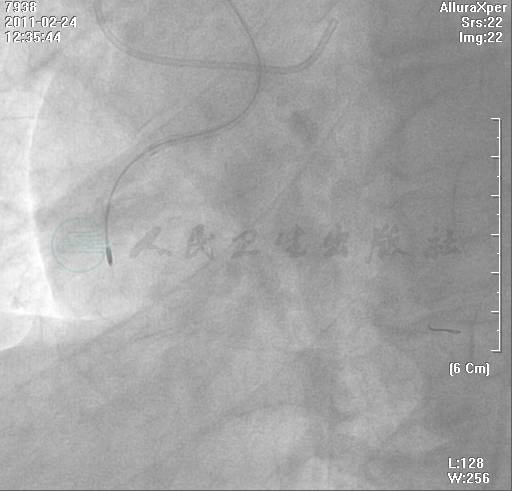

选用右侧桡动脉路径,6F动脉鞘。造影发现:左冠状动脉正常,可见间隔支到右冠状动脉远端侧支循环,右冠状动脉中远段完全闭塞,有残端,有自身桥侧支(图1~图3)。

图3 右冠造影

右冠造影显示右冠状动脉中远段完全闭塞,有残端,有自身桥侧支